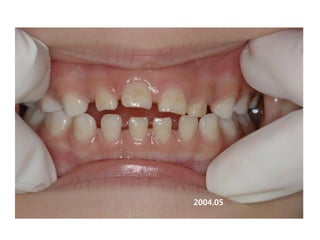

1999.04.05/F

C.C

• Diastema, flattened lower ant.

Dx

• Mentalis action, heavy labial frenum

Goal

• Establish normal lip tone

2006.02.08

2004.05.13

2006.12.27 10m

2007.05.08 1y 3m

2008.07.30 2y 5m

2009. 02.18.3y

2009.08.11 3y6m

2010.06.15 4y4m

2012 02 01

out of Tr 2yr